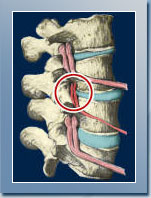

The term subluxation means minor misalignment. However the affects on the human body as a result of a subluxation on the upper cervical spine can be far from minor. In the simplest of terms, a subluxation is when one or more vertebrae (bones in your spine) move out of line and create pressure on spinal nerves. Spinal nerves are the nerves that come out from the vertebrae in your spine. Pressure on the nerves can cause interference with the signals traveling through them - leading to numerous health related problem.

Neuropathophysiology is where nerves can become overexcited and hyperactive. Due to the way the spine is engineered, abnormal spinal function can irritate, pinch, rub or choke the delicate tissue of the spinal cord and nerve roots.

Histiopathology is inflammation and swelling due to injured disc accompany the accumulation of blood and lymph - causing a rise in temperature.

Pathophysiology is when there is a trauma to a joint, one of the ways your body responds is the stabilization of the area by forming new bone! With time, calcium deposits build up, eventually as abnormal bony growth. This arthritic 'splinting' of bones is nature's attempt to stabilize the injured joint.